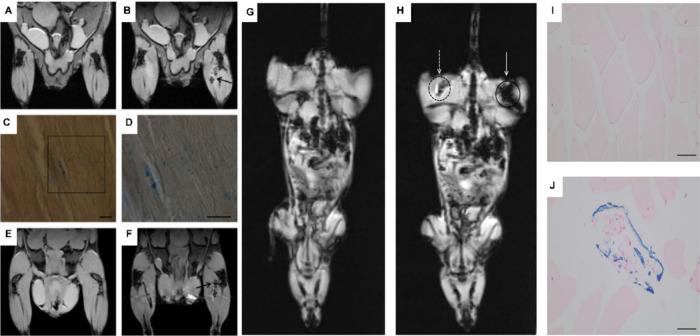

Mesenchymal stem-cell-derived extracellular vesicles (MSC-EVs) are nanoscale lipid bilayer vesicles secreted by mesenchymal stem cells. They inherit the parent cell's attributes, facilitating tissue repair and regeneration, promoting angiogenesis, and modulating the immune response, while offering advantages like reduced immunogenicity, straightforward administration, and enhanced stability for long-term storage. These characteristics elevate MSC-EVs as highly promising in cell-free therapy with notable clinical potential. It is critical to delve into their pharmacokinetics and thoroughly elucidate their intracellular and trajectories. A detailed summary and evaluation of existing tracing strategies are needed to establish standardized protocols. Here, we have summarized and anticipated the research progress of MSC-EVs in various biomedical imaging techniques, including fluorescence imaging, bioluminescence imaging, nuclear imaging (PET, SPECT), tomographic imaging (CT, MRI), and photoacoustic imaging. The challenges and prospects of MSC-EV tracing strategies, with particular emphasis on clinical translation, have been analyzed, with promising solutions proposed.